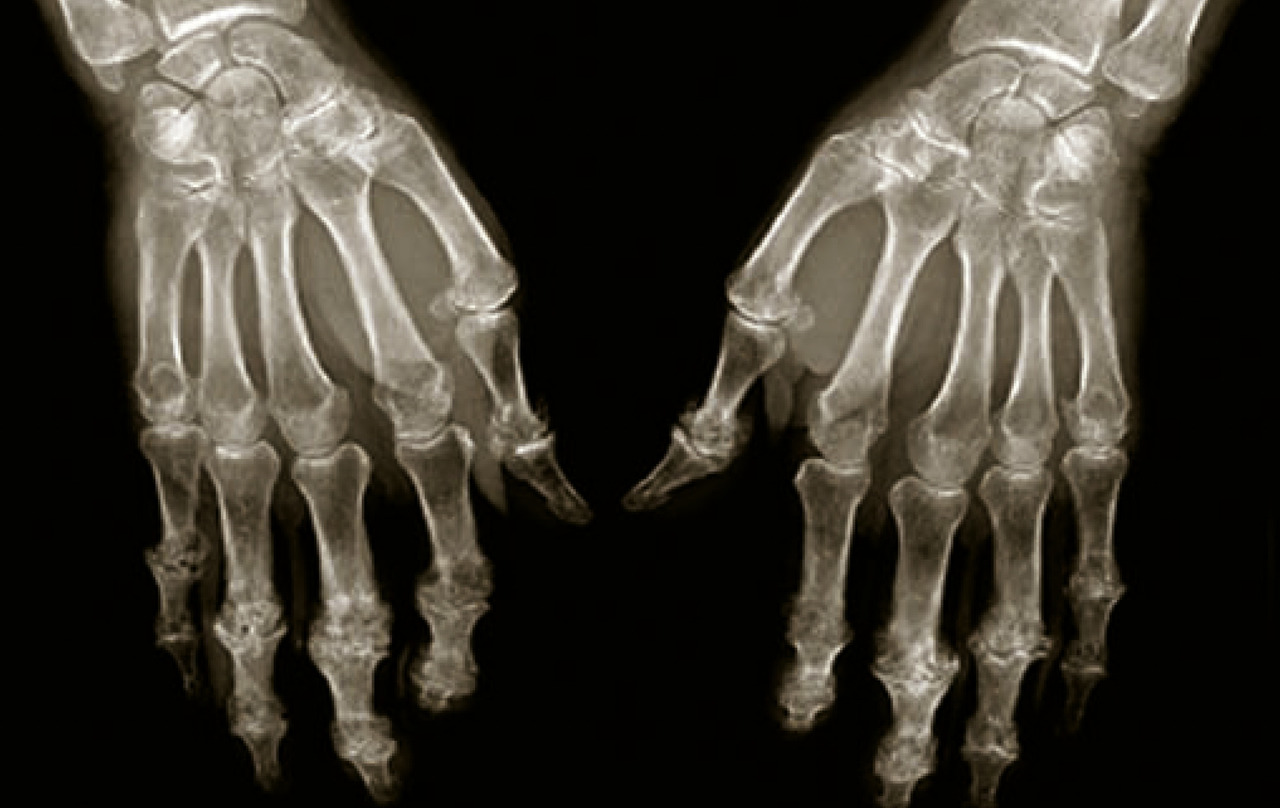

Arthrose digitale

C’est une arthrose intéressant les articulations inter­phalangiennes proximales (IPP), distales (IPD) et l’articulation trapézo-métacarpienne (appelée aussi rhizarthrose). Sa prévalence est estimée à environ un tiers des femmes et un quart des hommes. L’atteinte radiologique chez les patients âgés dépasse 80 %. La rhizarthrose est quasiment inexistante chez l’homme de moins de 50 ans tandis qu’elle est déjà présente chez 1 femme sur 10 à cet âge. Elle se développe souvent lors de la ménopause.

Examen clinique

Le diagnostic est clinique, et aucun examen complémentaire n’est nécessaire en cas de présentation typique. L’arthrose digitale débute fréquemment par un développement à bas bruit de tuméfactions nodulaires au niveau interphalangien distal (nodule d’Heberden) entraînant des déformations latérales ou en flessum, douloureuses et gênantes. Parfois, les tuméfactions atteignent les articulations interphalangiennes proximales (nodules de Bouchard), posant le problème d’un possible diagnostic différentiel de rhumatisme psoriasique. Dans ce cas, il peut être nécessaire de réaliser des examens complémentaires radiographiques et/ou biologiques.

Imagerie

Les radiographies sont inutiles au diagnostic. Quand elles sont effectuées, elles mettent en évidence un pincement des interlignes articulaires et une ostéophytose souvent exubérante correspondant cliniquement aux nodosités décrites précédemment (fig. 7). Pour la rhizarthrose (fig. 8), l’atteinte de cette articulation précède celle de la scapho-trapézienne.